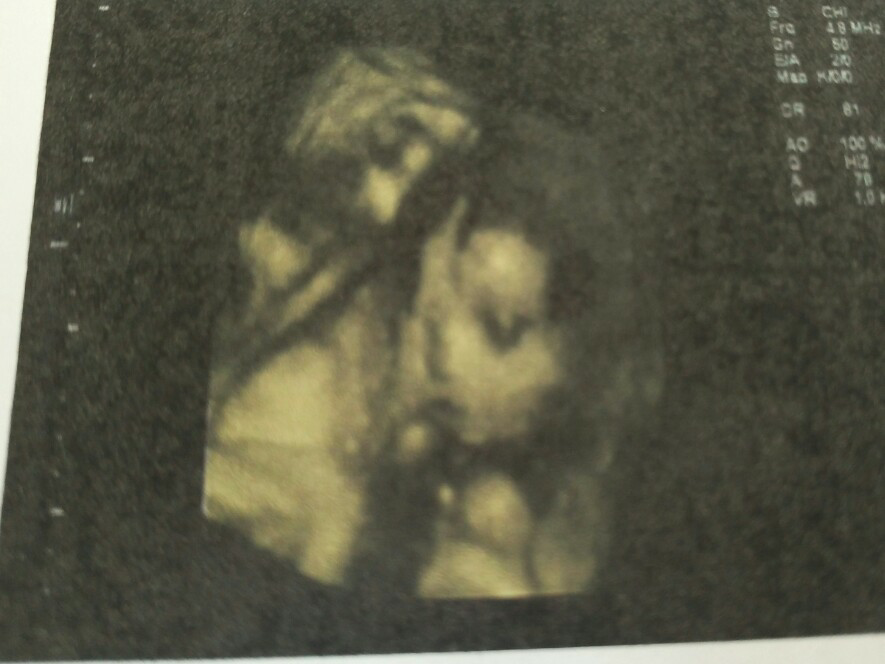

心快乐心想事成(附我家宝宝第一张照片,男宝哦[调皮])